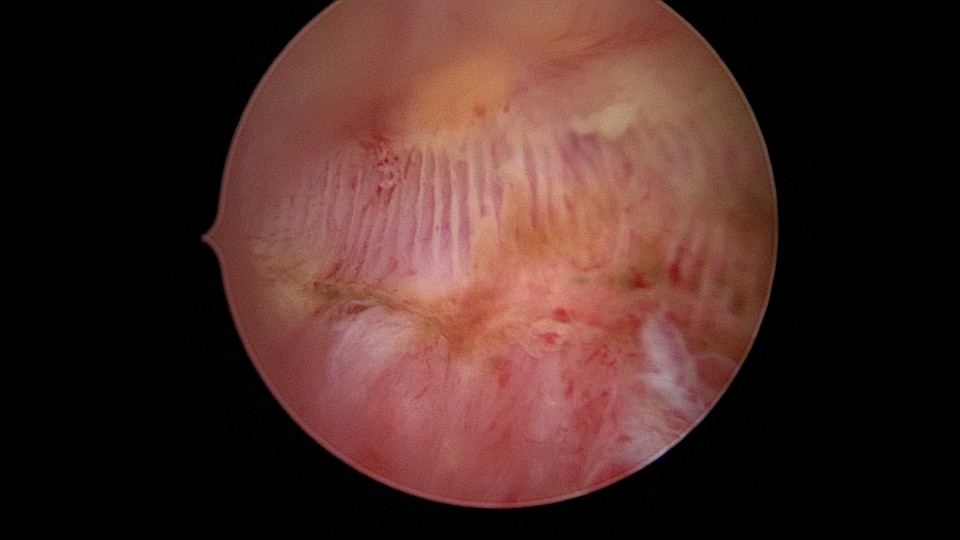

患者58岁,G2P1,顺产1次。安环35年,绝经15年,5年前在外院取环失败。术前B超提示子宫后位,O型环嵌顿,环顶端距宫底0.7cm。宫腔镜术中见阴道口狭小,无法置入窥阴器,宫颈外口狭窄,镜鞘缓慢扩大。宫颈内口粘连,左侧似有一小孔,异物钳扩大小孔,见较多浓稠黄色液体流出,冲洗干净后推进宫腔镜,见2个O型节育环,上面的环取出顺利,下面那个环与宫腔侧壁嵌顿,2次牵拉滑脱,第三次一张一驰松动节育环,再缓慢拉出,宫底见2道环压痕。